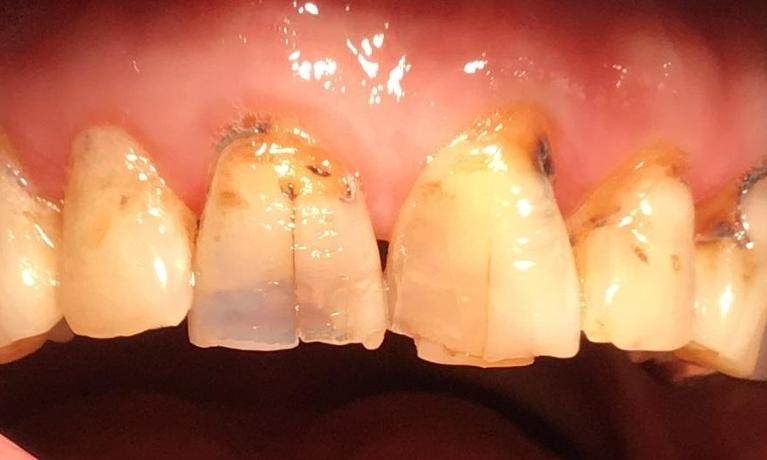

After cancer treatment, this patient was left with broken down front teeth. We rebuilt them with natural looking crowns so he can smile with confidence again!